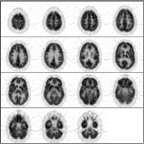

Click on image above to view full-size image.

This scan is too smooth.